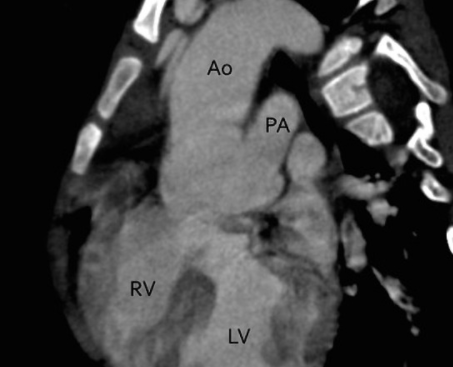

Tronc arteriel commun (TAC)

Truncus Arteriosis

- Aortie et Tronc pulmonaire à départ commun

- VSD

- Type I le plus fréquent (Tronc Pulm partant de la face postérieure gauche TAC)

- 1/3 associé à des arcs aortiques droits, avec cardiomégalie et vasculature pulmonaire augmentée (contrairement au fallot)